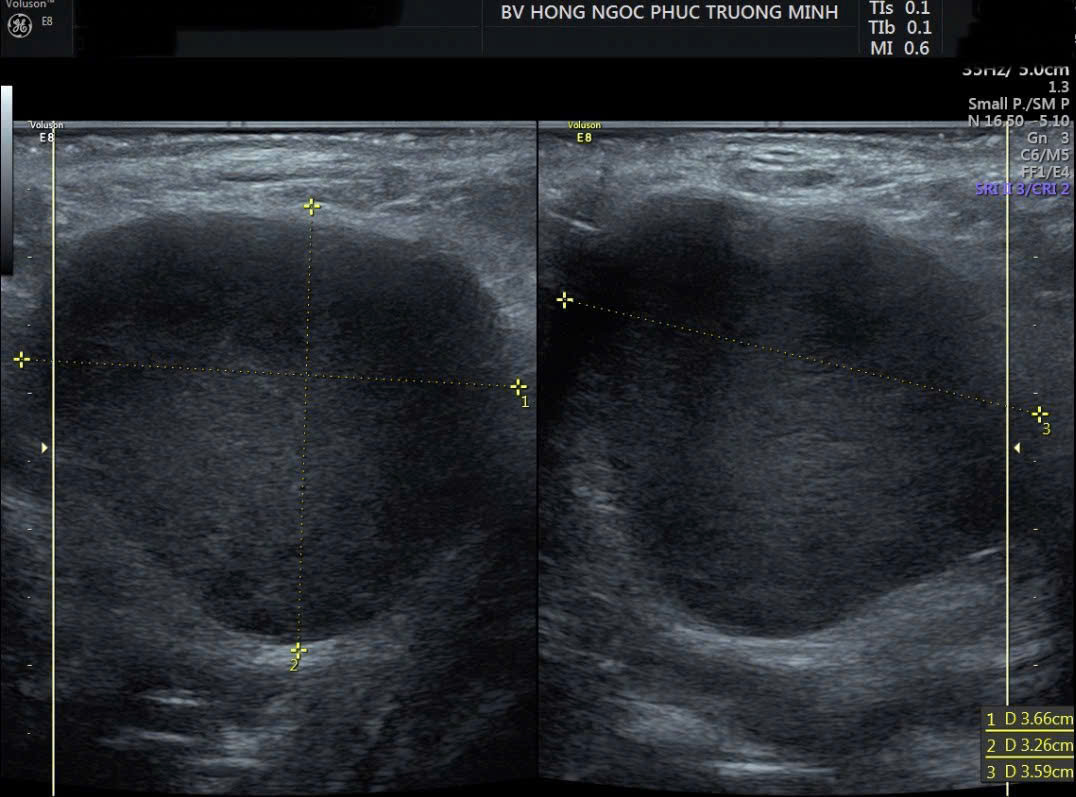

Qua thăm khám, các bác sĩ ghi nhận khối sưng kích thước 5x3cm tại môi lớn bên trái, đỏ, ấn đau. Kết quả siêu âm cho thấy hình ảnh nang tuyến Bartholin bội nhiễm - một bệnh lý phụ khoa tiềm ẩn nhiều biến chứng.

Khối nang Bartholin kích thước 5x3cm tại môi lớn bên trái của BN.